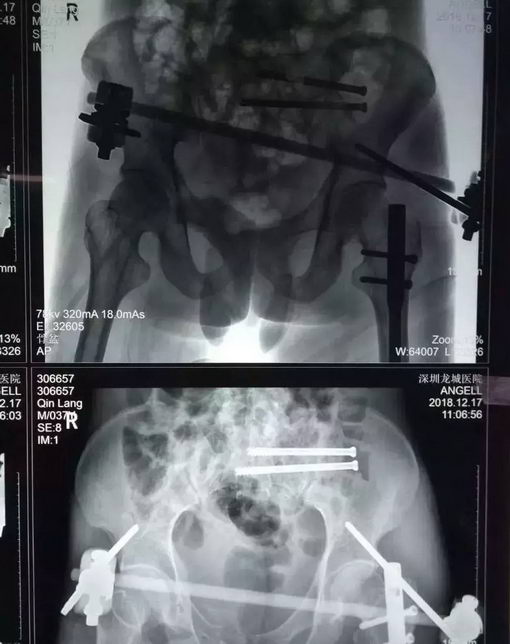

由于覃先生病情非常危重,医院立即开启绿色通道,紧急安排住进骨科抢救室。根据检查结果初步诊断覃先生为重症多发伤。骨科博士汪金平详细介绍说,患者的主要诊断包括:① 创伤性休克;② 骨盆多发不稳定骨折:左侧骶骨粉碎性骨折、右侧耻骨上下支粉碎性骨折;③ 左侧股骨干骨折;④ 右侧踝关节骨折;⑤ 急性失血性贫血等情况。

影像资料显示,患者骶1椎存在发育畸形,这种骶骨畸形增加了实施骶髂螺钉固定的风险,因为骶骨里和周围有大量的神经和血管呈网状分布,手术中一点偏差可能造成无法挽回的严重后果,轻者损伤神经造成患者瘸腿,重者损伤血管导致大出血而造成患者死亡。

12月14日,在患者伤后第三天,由博士带领团队为患者施行了透视下实施经皮骶髂螺钉固定术,首先闭合复位骨盆骨折成功,即刻经皮置钉完成前环外固定架固定术以稳定骨盆。然后顺利地经骶1椎和骶2椎各置入一枚骶髂螺钉固定,至此骨盆的前后环均获得牢固固定。手术历时近2小时,所有切口加起来的总长度不超过5cm,手术中出血不到10毫升。术后复查显示骨折复位和内固定位置都很好,医生评估预计手术后三个月可以正常行走。